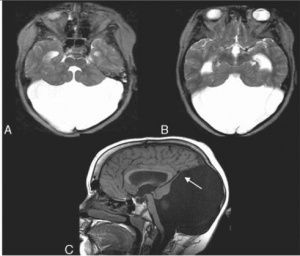

Mega sisterna magna, sisterna magnanın 10 mm’den daha geniş ölçülmesidir. Dördüncü ventrikül normal bulunur ve serebeller hemisferler normal görünümdedir. Aynı şekilde serebeller vermis tamdır ve normal yapıdadır.

Mega sisterna magna tanısı konulurken Dandy-wolker malformasyonu, normal erken beyin gelişimi, araknoid kist ve Galen ven malformasyonları ile ayırıcı tanısının yapılması gerekir.